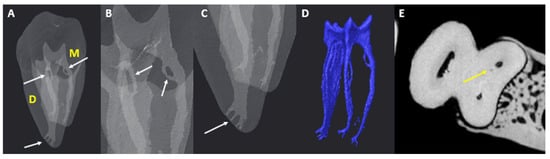

3.5. Accessory Canals (ACs)

3.5.1. M Root

3.5.2. D Root